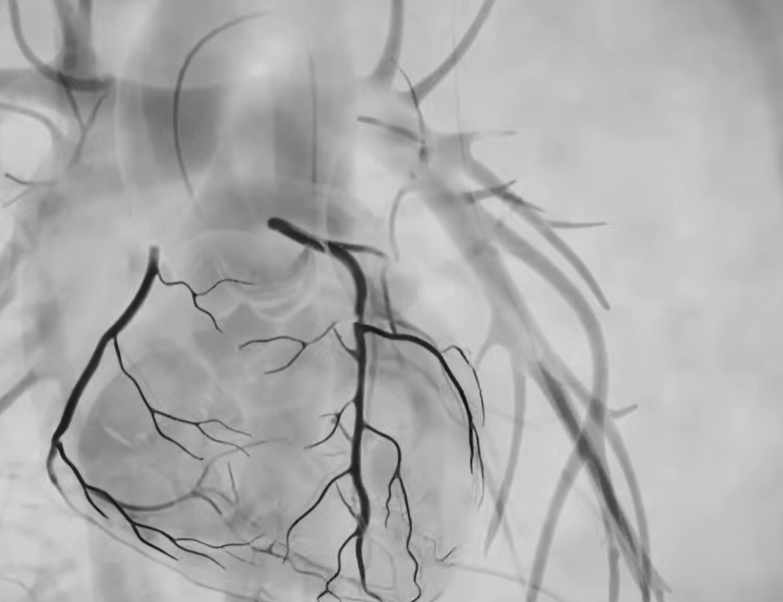

단순한 초음파나 CT와 달리, 조영제를 혈관 안에 넣어 막힘 위치와 정도를 실시간 영상으로 확인하기 때문에 협심증·심근경색 진단의 표준 검사로 사용됩니다. 증상이 애매할수록, 검사 결과가 치료 방향을 크게 좌우하기 때문에 중요한 의미를 갖습니다.

검사는 보통 손목(요골동맥)이나 사타구니 혈관을 통해 가느다란 관을 넣어 심장 혈관까지 이동시킨 뒤, 조영제를 주입하며 X-ray로 촬영합니다.